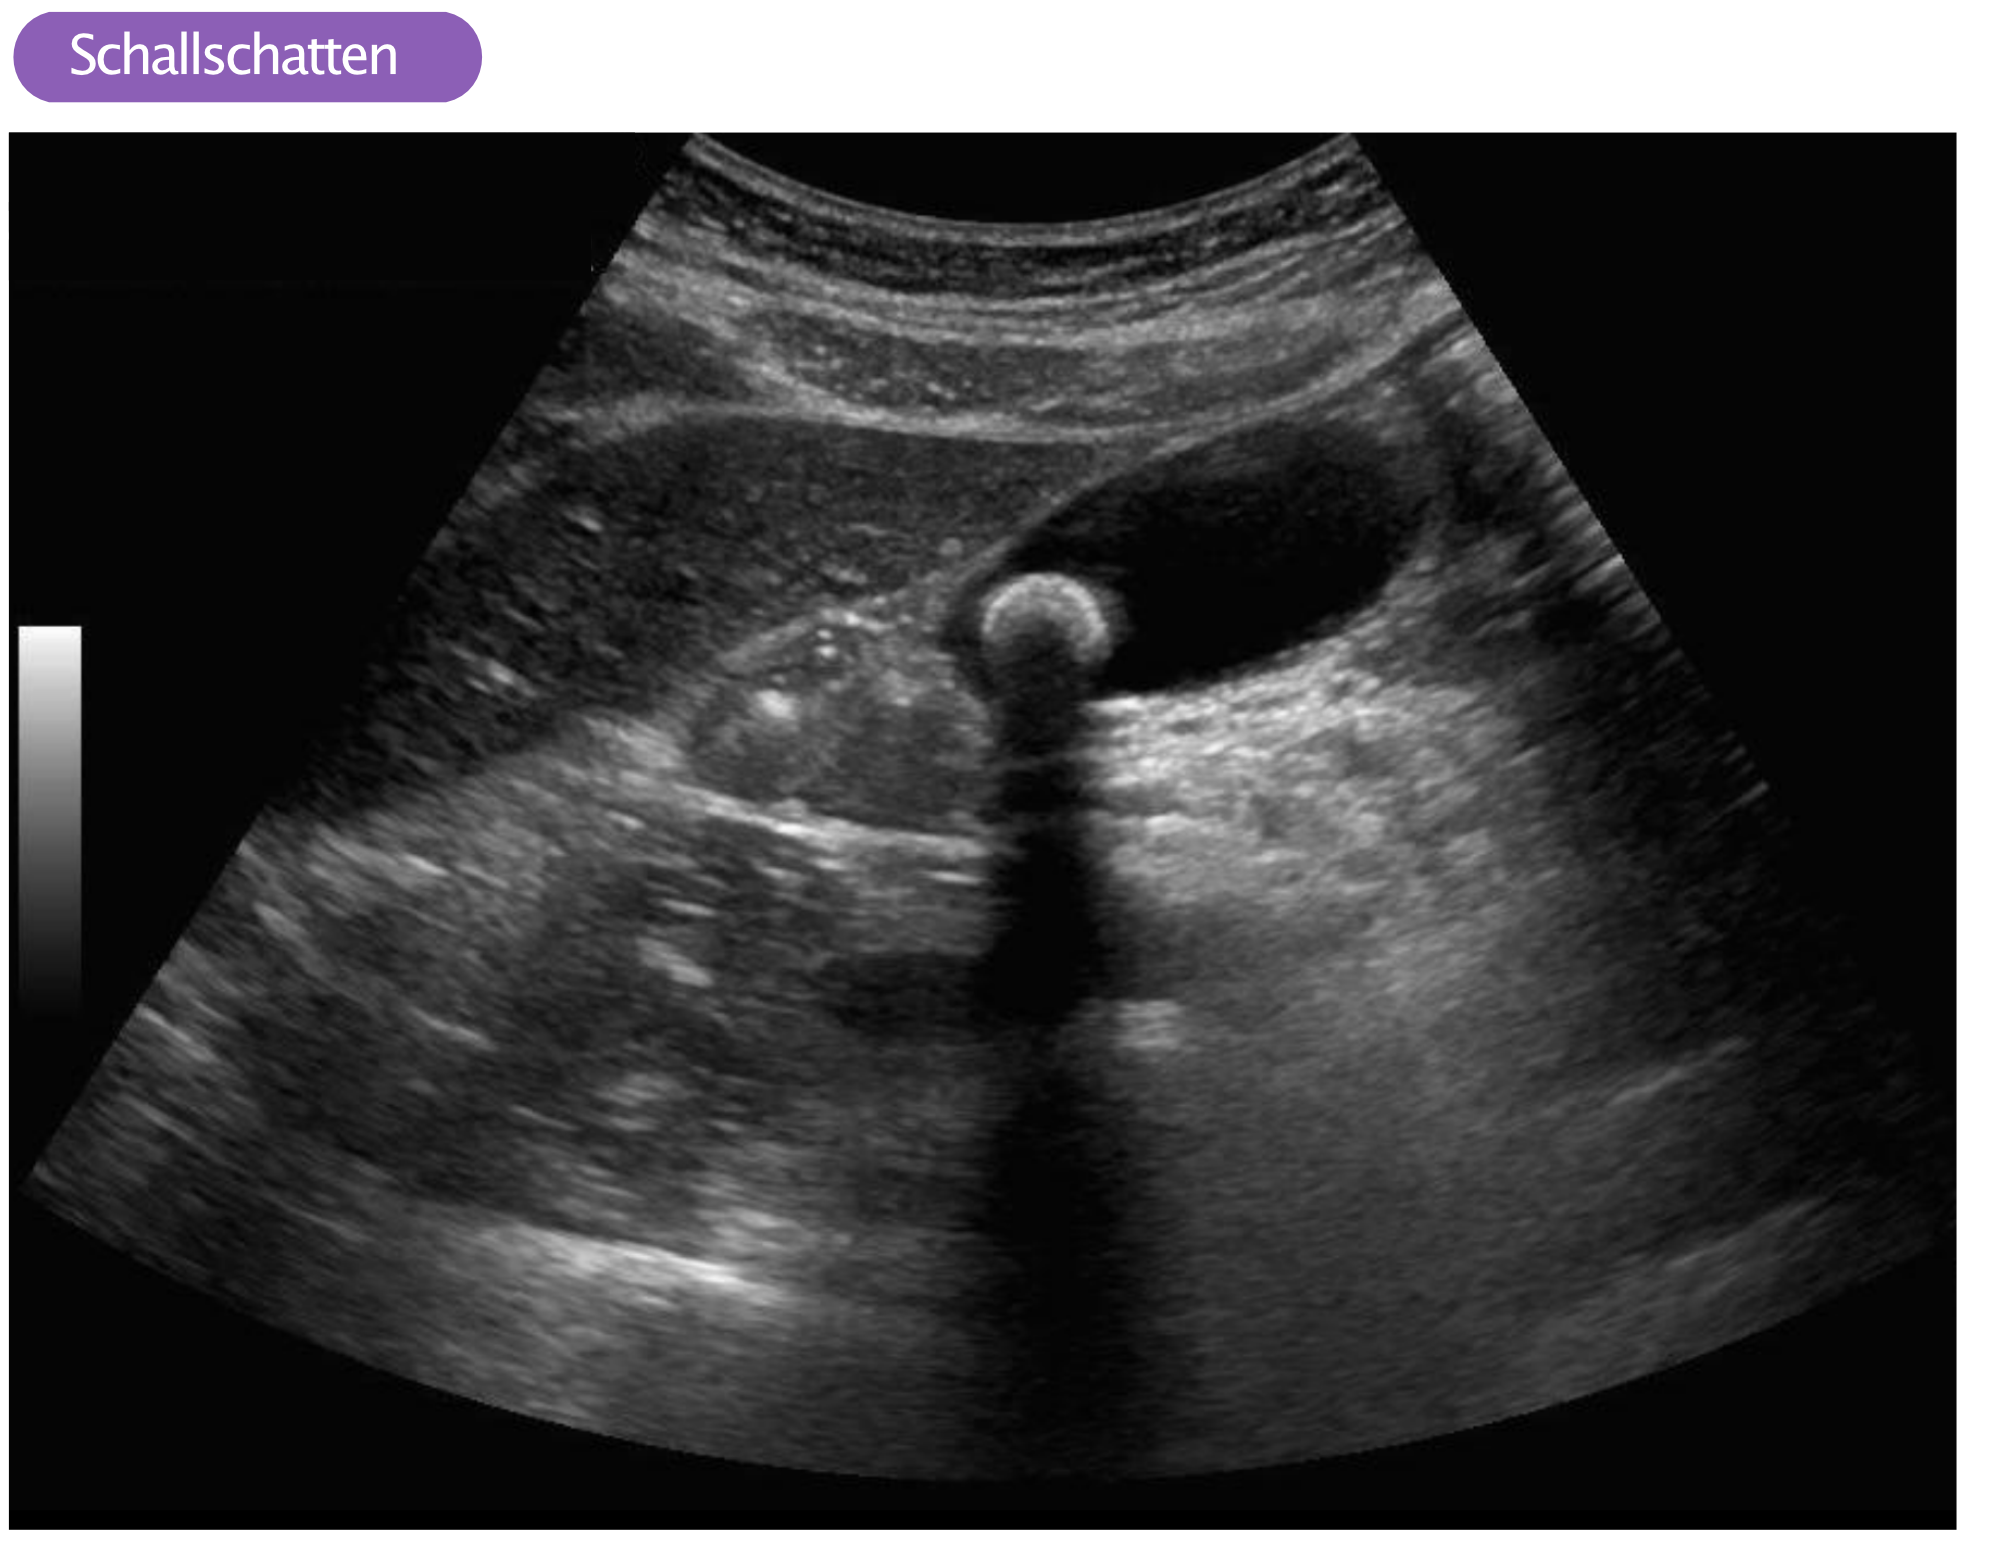

Artefakte in der Ultraschallbildgebung EKG & ECHO Motion Artifact Ultrasound We show how speckle decorrelation and convolutional neural networks methods can be related, and describe a network architecture. An artifact is something that you see on the ultrasound image which is either not really there, is in another place in reality, or looks different than it actually. Ultrasound artifacts are commonly encountered and familiarity is necessary to avoid false diagnoses.. Motion Artifact Ultrasound.